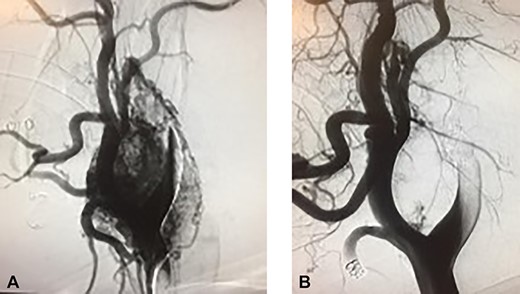

Incision was made from the angle of the mandible towards the chin and subplatysmal flaps were created. The common carotid artery was dissected to obtain proximal control. Distal control was obtained by exposing the internal carotid artery and the ECA cephalad to the tumor (Fig. 3). The tumor was adherent to the posterior wall of the carotid bifurcation, requiring en-bloc resection (Fig. 4) with reconstruction using a common carotid to internal carotid bypass performed with a 6-mm polytetrafluoroethylene (PTFE) interposition graft (Fig. 5). The hypoglossal, vagus and glossopharyngeal nerves were identified, meticulously dissected and preserved. The patient recovered well, had hoarseness of the voice, which resolved after few months with no intervention. The tumor pathology revealed an extra-adrenal paraganglioma positive for chromogranin, synaptophysin and S-100.

CBTs specimen, posterior view with the bifurcation attached to it.